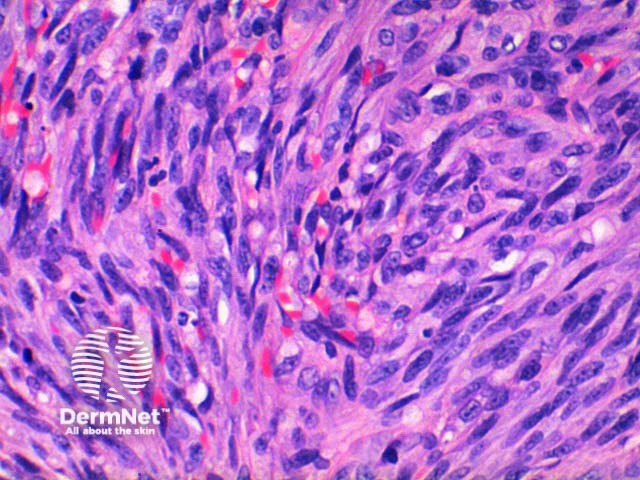

The low power view of the histology of Kaposi sarcoma is of a cellular dermal nodule (Figure 1). There may be varying degrees of overlying epidermal changes which can range from prominent hyperkeratosis and acanthosis to frank ulceration. The dermal proliferation is comprised of a spindle cell proliferation of endothelial cells forming sinuous vascular spaces. These may be sparse in patch phase lesions, progressing to fascicles of spindle cells in nodular lesions (Figures 2,3). This fascicular pattern has been likened to schools of fish. The spindle cells infiltrate through the collagen, forming slit-like spaces, especially towards the periphery of the lesions (Figure 4). Where the newly formed vessels project into an existing space the promontory sign is seen (Figure 5). This is now recognised as not being specific to this condition.

In plaque and nodular stage lesions, there may be visible intracellular and extracellular hyaline globules, though to represent engulphed erythrocytes. While rare this may be seen in patch stage lesions. They stain PAS positive. While the endothelial proliferation is frequently monomorphic, there may be significant nuclear atypia with increased mitotic activity (Figure 6). When prominent atypia is seen the tumour fits into the category of an anaplastic variant.

The inflammatory infiltrate is predominantly lymphocytic with scattered plasma cells also a clue to this diagnosis. Erythrocytes are seen within the slit-like spaces and throughout the tumour. Sometimes at the base and periphery of nodular Kaposi, there may be large cavernous vessels.

Figure 3

Figure 4